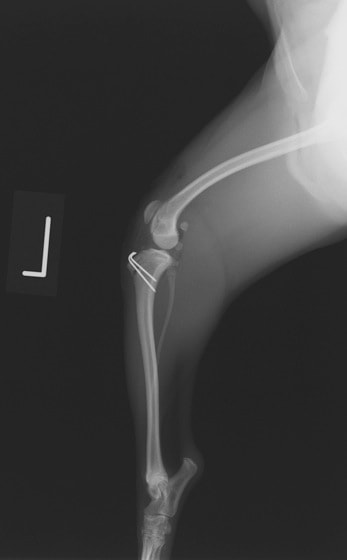

■ 症例24 キャバリア 7か月

左右膝蓋骨内方脱臼(左:グレードⅣ 右:グレードⅢ)

以前から左右後肢の跛行が認められ、整形外科学的検査・レントゲン検査により左右の膝蓋骨脱臼が認められた。症状が重度である左膝の膝蓋骨脱臼整復術を行った。外科手技は縫工筋及び内側広筋の解放、脛骨粗面の外側転位、滑車ブロック形造溝術、内外側関節方の縫縮を実施した。術後一か月時点で、左の膝蓋骨は安定しており経過は良好である。

本症例は成長期における重度の膝蓋骨脱臼であり、術後の再発の可能性もあるため、経過をしっかりと観察していく必要がある。また、今回手術を実施していない右膝に関しても経過を観察し、手術を検討していくこととする。